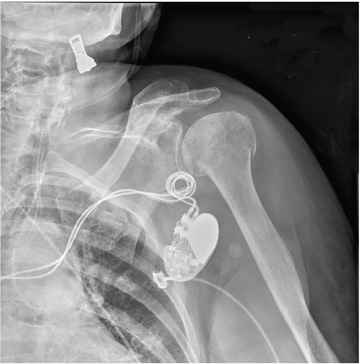

A 90-year-old woman is transferred to your facility from an outside hospital for evaluation of an intracranial hemorrhage secondary to a fall. The patient normally resides in a nursing home and has dementia. She was reportedly ambulating with her walker when she tripped and fell forward. In addition to dementia, her medical history is significant for sick sinus syndrome, for which she has a pacemaker. She also has hypertension and degenerative joint disease. Examination reveals an elderly female who is alert but very confused. Her vital signs are normal. She has moderate swelling and bruising on the left side of her forehead and left orbit. Her pupils react well. As you examine her, you note her unwillingness to use or move her left arm. When you inquire, she states, “It hurts.” Close examination of the left upper extremity shows no obvious deformity or swelling. She does have some tenderness over the left shoulder. You order a radiograph of the left shoulder (shown). What is your impression?

The radiograph demonstrates significant osteopenia. In addition, there is a slightly impacted subcapital fracture of the humeral neck.

Orthopedics was consulted, and the patient was to be treated with nonoperative management. She was given a swathe for immobilization and comfort.